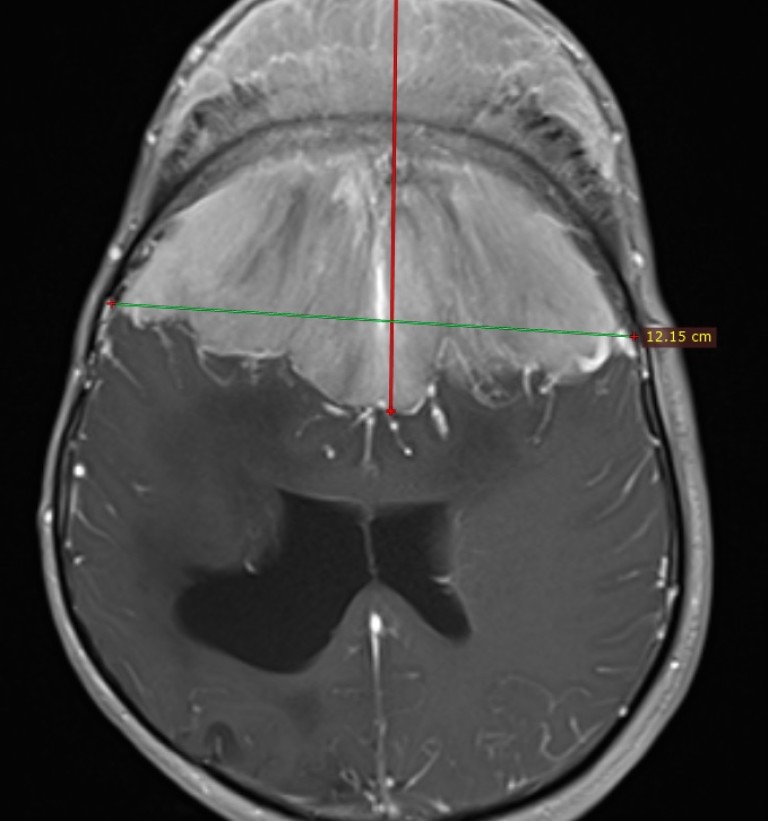

Уникална операция за отстраняване на огромен тумор с тегло над 1 кг от мозъка на мъж бе направена в МБАЛ "Св. Иван Рилски" преди дни. Екипът, извършил операцията, която е първата по рода си в Европа, разказа за случая.

Осем часа е продължила тежката операция на 41-годишния Божидар на 4 ноември. Мъжът години наред е страдал от главоболие, зрението му намалявало, а главата видимо се деформирала.

След свикване на екип за операцията и обсъждане на случая, след проучване, че има само няколко такива случая в света, е решено мъжът да бъде опериран с нов подход. Първо се запушват хранещите съдове на тумора, а след ден се пристъпва към операцията и отстраняване на лезията.